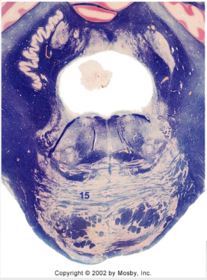

| Medullary pyramids | |

| Hypoglossal nucleus | |

| Hypoglossal nerve | |

| Dorsal motor nucleus of X | |

| Nucleus ambiguus | |

| Solitary tract | |

| Solitary nucleus | |

| ALS | |

| Medial lemniscus | |

| Medial longitudinal fasciculus | |

| Anterior spinocerebellar tract | |

| CN IX | |

| Inferior cerebellar peduncle | |

| Inferior olivary complex | |

| Dorsal cochlear nucleus | |

| Inferior vestibular nucleus | |

| Medial vestibular nucleus | |

| Spinal nucleus of V | |

| Spinal tract of V | |